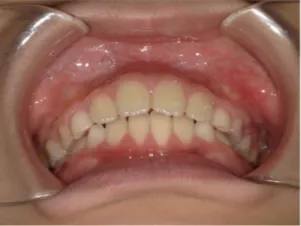

治療中③中1:拡大・前歯の並替え、トイシャー(出っ歯を治す装置)終了

*出っ歯、過蓋咬合、口唇閉鎖不全の改善

*咬合治療用モノブロック装置(筋機能的咬合誘導装置)へ移行

*口唇閉鎖不全がなおり奇麗な口元に改善

*就寝時に使用するモノブロック装置(筋機能的咬合誘導装置)